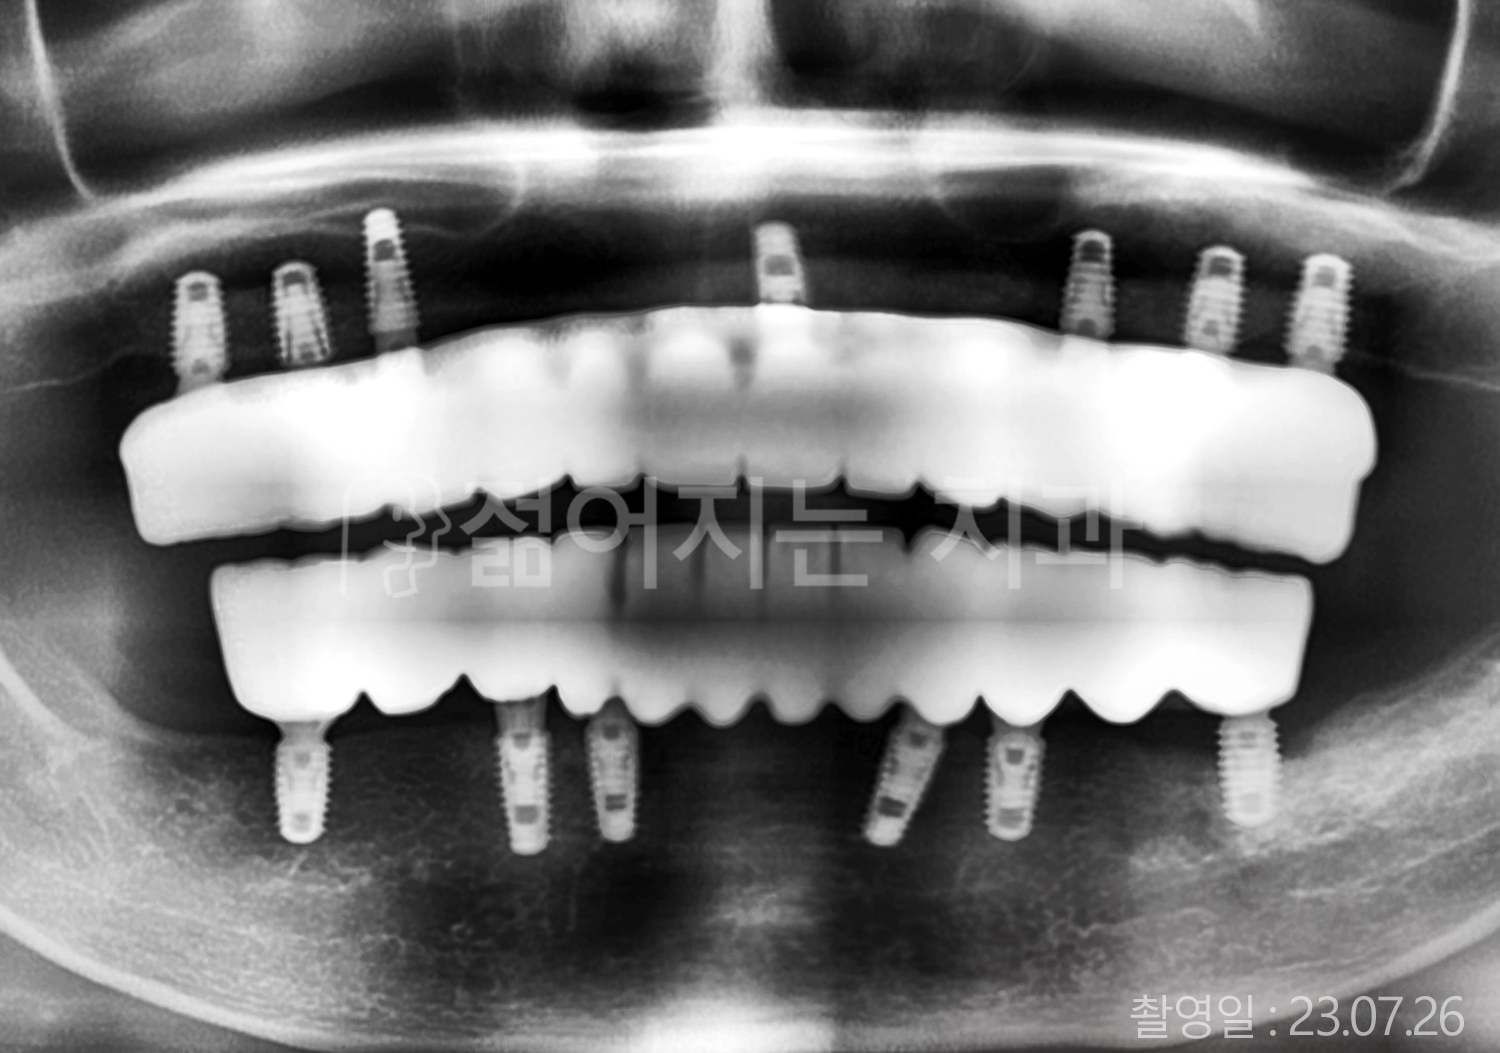

• 50대 고혈압, 당뇨, 고지혈증 전체치아 10개 이상 임플란트

• 60대 골다골증, 간경화 전체치아 10개 이상 임플란트

• 60대 고혈압, 고지혈증 전체치아 10개 이상 임플란트

• 50대 고혈압, 당뇨 전체치아 10개 이상 임플란트

• 60대 고혈압 전체치아 10개 이상 임플란트

• 60대 전체치아 10개 이상 임플란트

• 60대 고지혈증 전체치아 10개 이상 임플란트

• 40대 전체치아 10개 이상 임플란트

• 70대 전체치아 10개 이상 임플란트